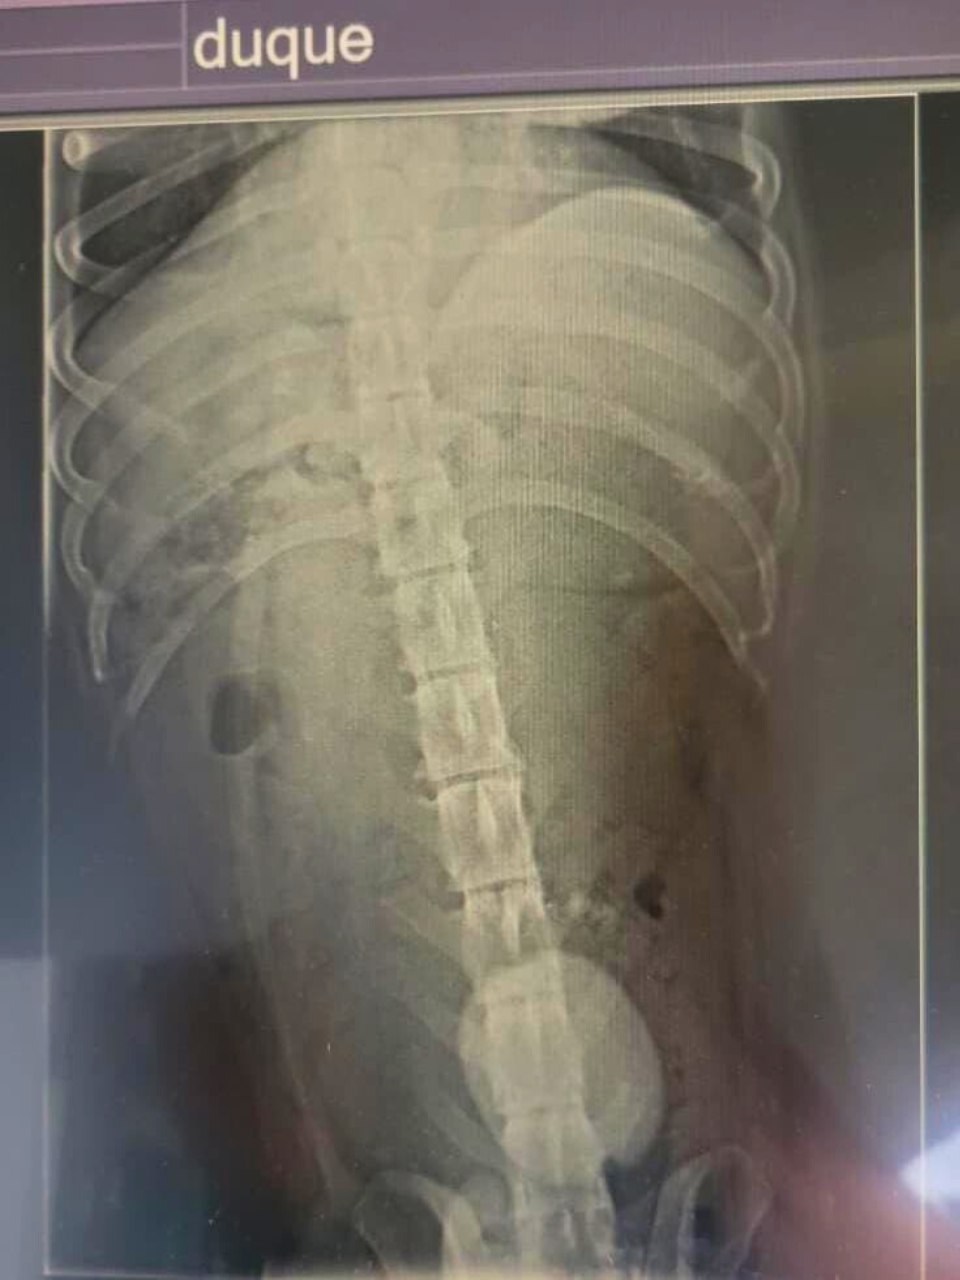

Meet Duque, a beloved dog from San Cristóbal in the Galapagos. His owner brought him to the World Vets small animal clinic after noticing something wasn’t right. During his exam, our veterinary team discovered a massive bladder stone on the x-ray—a painful and serious condition!